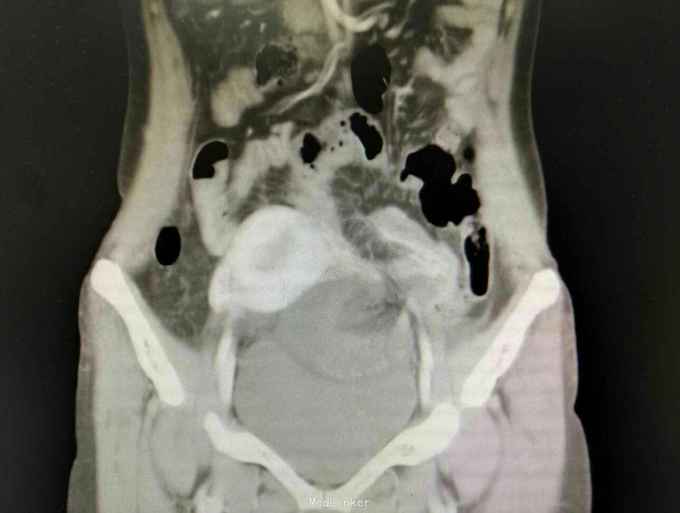

入院后急查血象稍高,完善急诊CT示内疝并闭袢性肠梗阻,予急诊行剖腹探查,术中见子宫右移,距离回盲部50cm回肠内疝入子宫与前腹壁所形成的黏连中,松解黏连,见回肠约15cm缺血坏死,予切除后吻合,缝闭黏连所造成的腔隙,关腹。术后常规治疗,患者回复可予出院。病理如图。

患者腹痛入院,各项生命体征平稳,无腹膜炎体征,抽血也没较大的异常,常规来说并不需要特殊处理,所幸的是完善了CT,及时发现了腹痛原因,因黏连形成的腔隙与腹腔隔离,所以患者腹痛不明显,即使肠坏死一般情况也无特殊,患者发病时间短,CT检查及时,避免了延误治疗导致肠坏死加剧。从中我们可以吸取教训,对于急腹症腹痛不典型的患者,不能用某种炎症解释病情的话,如果既往有手术病史,一定要注意内疝可能,对当前的医疗环境来说,急诊CT可以帮助明确诊断